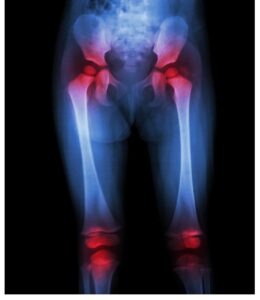

כאב ירכיים

כאשר שכבת הסחוס ניזוקה בין מפרק הירך

ולא מצליחה למזער את החיכוך בין עצמות הירך,

יש סיכוי גבוה יותר למפרק הירך להיות מותקף על ידי מחלת מפרקים.

זה גם בגלל תהליך ההזדקנות כאשר המפרקים והעצמות

נוטים להיחלש ככל שהזמן מתקדם.

כך הוא מוביל את עצמות הירך והמפרקים להפוך לצורה שבירה וחלשה יותר.

כתוצאה מכך, תחווה קושי בתנועת מפרק הירך.